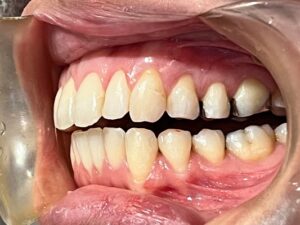

今回は、前歯のレイヤリングジルコニアセラミックの

治療をされた患者さまのご紹介です!

歯周治療、虫歯治療、審美治療の総合的な治療をおこないました。

修復の材料はほぼジルコニアセラミッククラウンで統一しています。

天然の歯は事前にホワイトニングを行い、全体的にトーンアップさせて、

それに合わせてカラーを決めています。

前歯のレイヤリングジルコニアはセラミストのデジタルトライインを行って

作製します!

全体的に綺麗になって患者さまもとても喜んでおられました♪